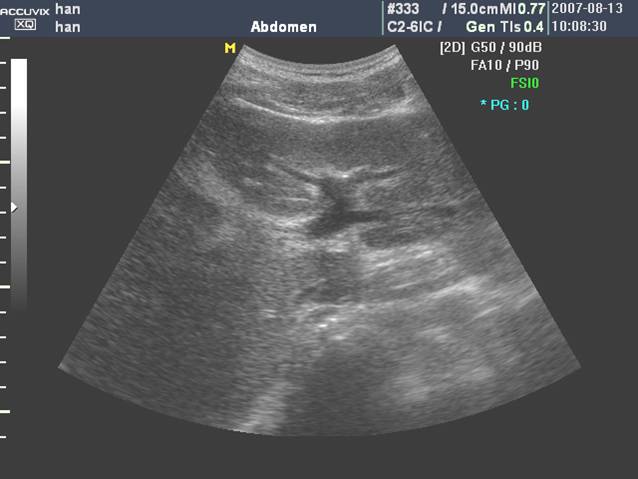

(二)门静脉

门静脉主干是由肠系膜上静脉和脾静脉在胰颈背侧汇合而成,居于胆总管和肝动脉之后。

门静脉从第一肝门开始,分左右两大支。左支沿横沟向左侧横行行走,名左支横段,待抵达左内、外叶交界处,折向足端走,与横段垂直,形成独特的“C”形结构称矢状段, 末端稍膨大称囊部,与肝圆韧带相连,后者为脐静脉闭锁后的残迹。

门静脉左干横部、矢状部及左内叶支和左外叶上、下段支的空间投影图像呈“工”字形:

门静脉右支较短,约1.5cm左右,向右水平走行分成右前支和右后支,前支和后支分别再分成上段支和下段支:

门静脉右干及分支,当探头沿着门静脉主干右上方移动可显示右干,其远端“Y”型分叉:

门静脉主干及右支长轴和胆囊长轴呈空间"垂直",立体投影空间排列呈"飞鸟样":